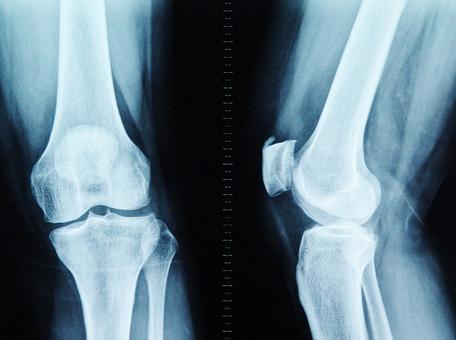

在人体的“骨骼大厦”中,胶原蛋白是钢筋,钙、镁、磷等骨质就是水泥。30岁后,胶原蛋白流失加剧,胶原框架老化变细、变脆甚至断裂,出现缺口;钙、镁、磷等骨质无法正常沉积在骨骼上,从缺口中游离出来;随着肢体的活动和负重,游离的骨质慢慢堆积在活动频繁、承重量大的关键部位(如颈椎、腰椎、膝关节、足跟),骨刺由此产生。

骨刺与人体原有骨骼结构相似,成分相同,因此单纯通过理疗或止痛膏贴产品根本无法达到真正的消解效果,只能依靠骨重建让增生骨质被自身骨组织慢慢分解、代谢、吸收。